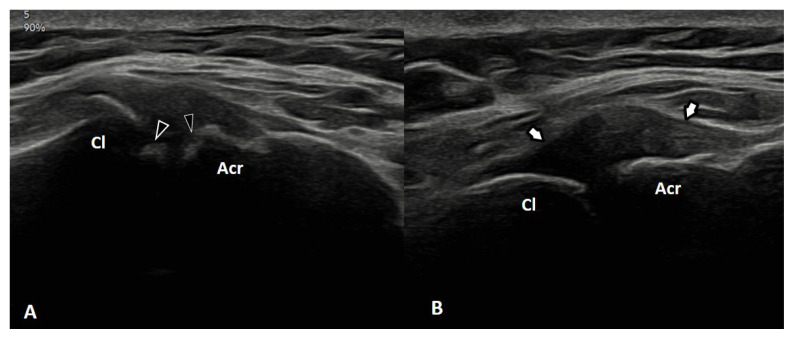

Results: While the shoulder joint accounted for the majority of joint pain detected in 23 patients, bursitis was the most common sonographic pathology. As a result of clinical and sonographic evaluations, it was determined that 29 patients had overuse syndrome. The likelihood of developing overuse syndromes increased with longer daily wheelchair use (OR = 1.666; p = 0.048) and high lesion level (OR = 12.01; p = 0.052). It decreased with the SF-36 pain score (OR = 0.943; p = 0.027).

Conclusion: The shoulder joint was the most commonly affected area in terms of pain, sonographic findings, and overuse syndrome. Prolonged daily wheelchair use, thoracic-level lesions, and lower SF-36 pain subscale scores might be determinants of the development of upper extremity overuse syndromes in paraplegic wheelchair users.